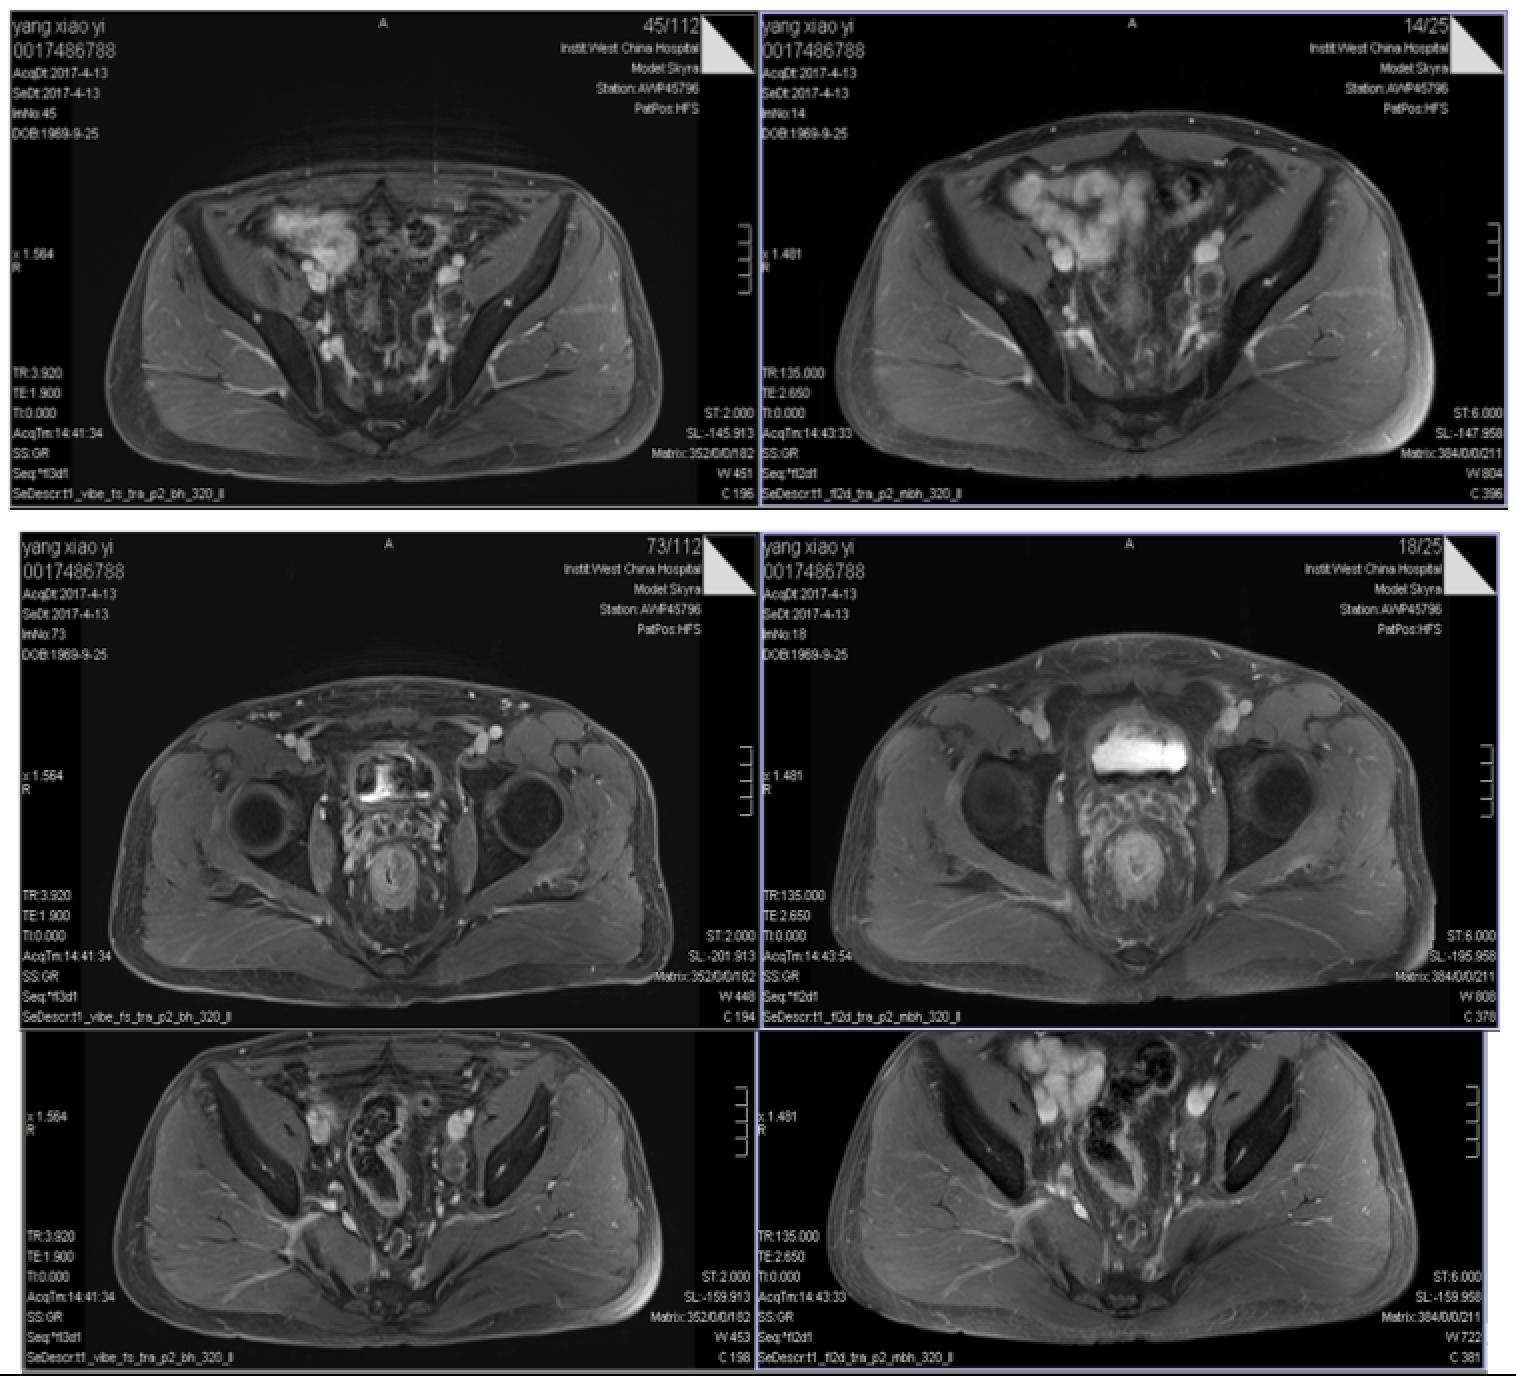

直肠MRI

DIS:直肠肿瘤位于:中下段,位于腹膜反折上、下,肿瘤下极距肛下缘约4.8cm。

T:肿瘤中心位于直肠后壁;侵及肠壁(突出浆膜、外膜);直肠系膜受累及(侵出肠壁约1.9cm),距离直肠系膜环周0.5cm。

A(肛管):肿瘤未累及侵犯肛管。

N(淋巴结):直肠系膜区及盆腔多发增大淋巴结,DWI呈高信号,T2WI呈高信号,最大位于左侧髂血管旁,直径约2.7cm。

C(CRM,环周切缘):增大淋巴结距离直肠系膜周边最近距离<1mm,系膜环周筋膜受累。

E(EMVI,壁外血管侵犯):直肠周围静脉丛可疑受侵犯

直肠中下段癌,距肛下缘4.8cm,位于腹膜反折上、下,肛管未受累,直肠系膜区及盆腔多发肿大淋巴结,环周切缘阳性,壁外血管可疑受侵犯。

DIS:直肠肿瘤位于:中下段,位于腹膜反折上、下,肿瘤下极距肛下缘约4.5cm。

N(淋巴结):直肠系膜区及盆腔多发增大淋巴结,DWI呈高信号,T2WI呈高信号,最大位于左侧髂血管旁,直径约4.0cm。

E(EMVI,壁外血管侵犯):直肠周围静脉丛可疑受侵犯。

直肠中下段癌,距肛下缘4.5cm,位于腹膜反折上、下,肛管未受累,直肠系膜区及盆腔多发肿大淋巴结,环周切缘阳性,壁外血管可疑受侵犯。

肝右叶小囊肿。

双肾多个小囊肿。

DWI